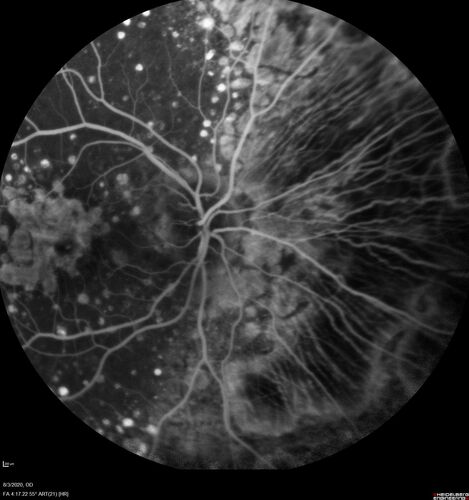

Age-related macular degeneration - Geographic Atrophy - Intermittent CME left eye from CRVO, Anemia, Diabetes

79 year old female - 3 years post CRVO in the left eye (20/32 VA) with intermittent CME.  Left eye is the better eye.  Vision is stable since 2 years ago

PMHx: Type II DM x 20 years, Chronic Anemia, Hyperlipidemia

VA 20/200 OD, 20/50 OS (usually 20/40)